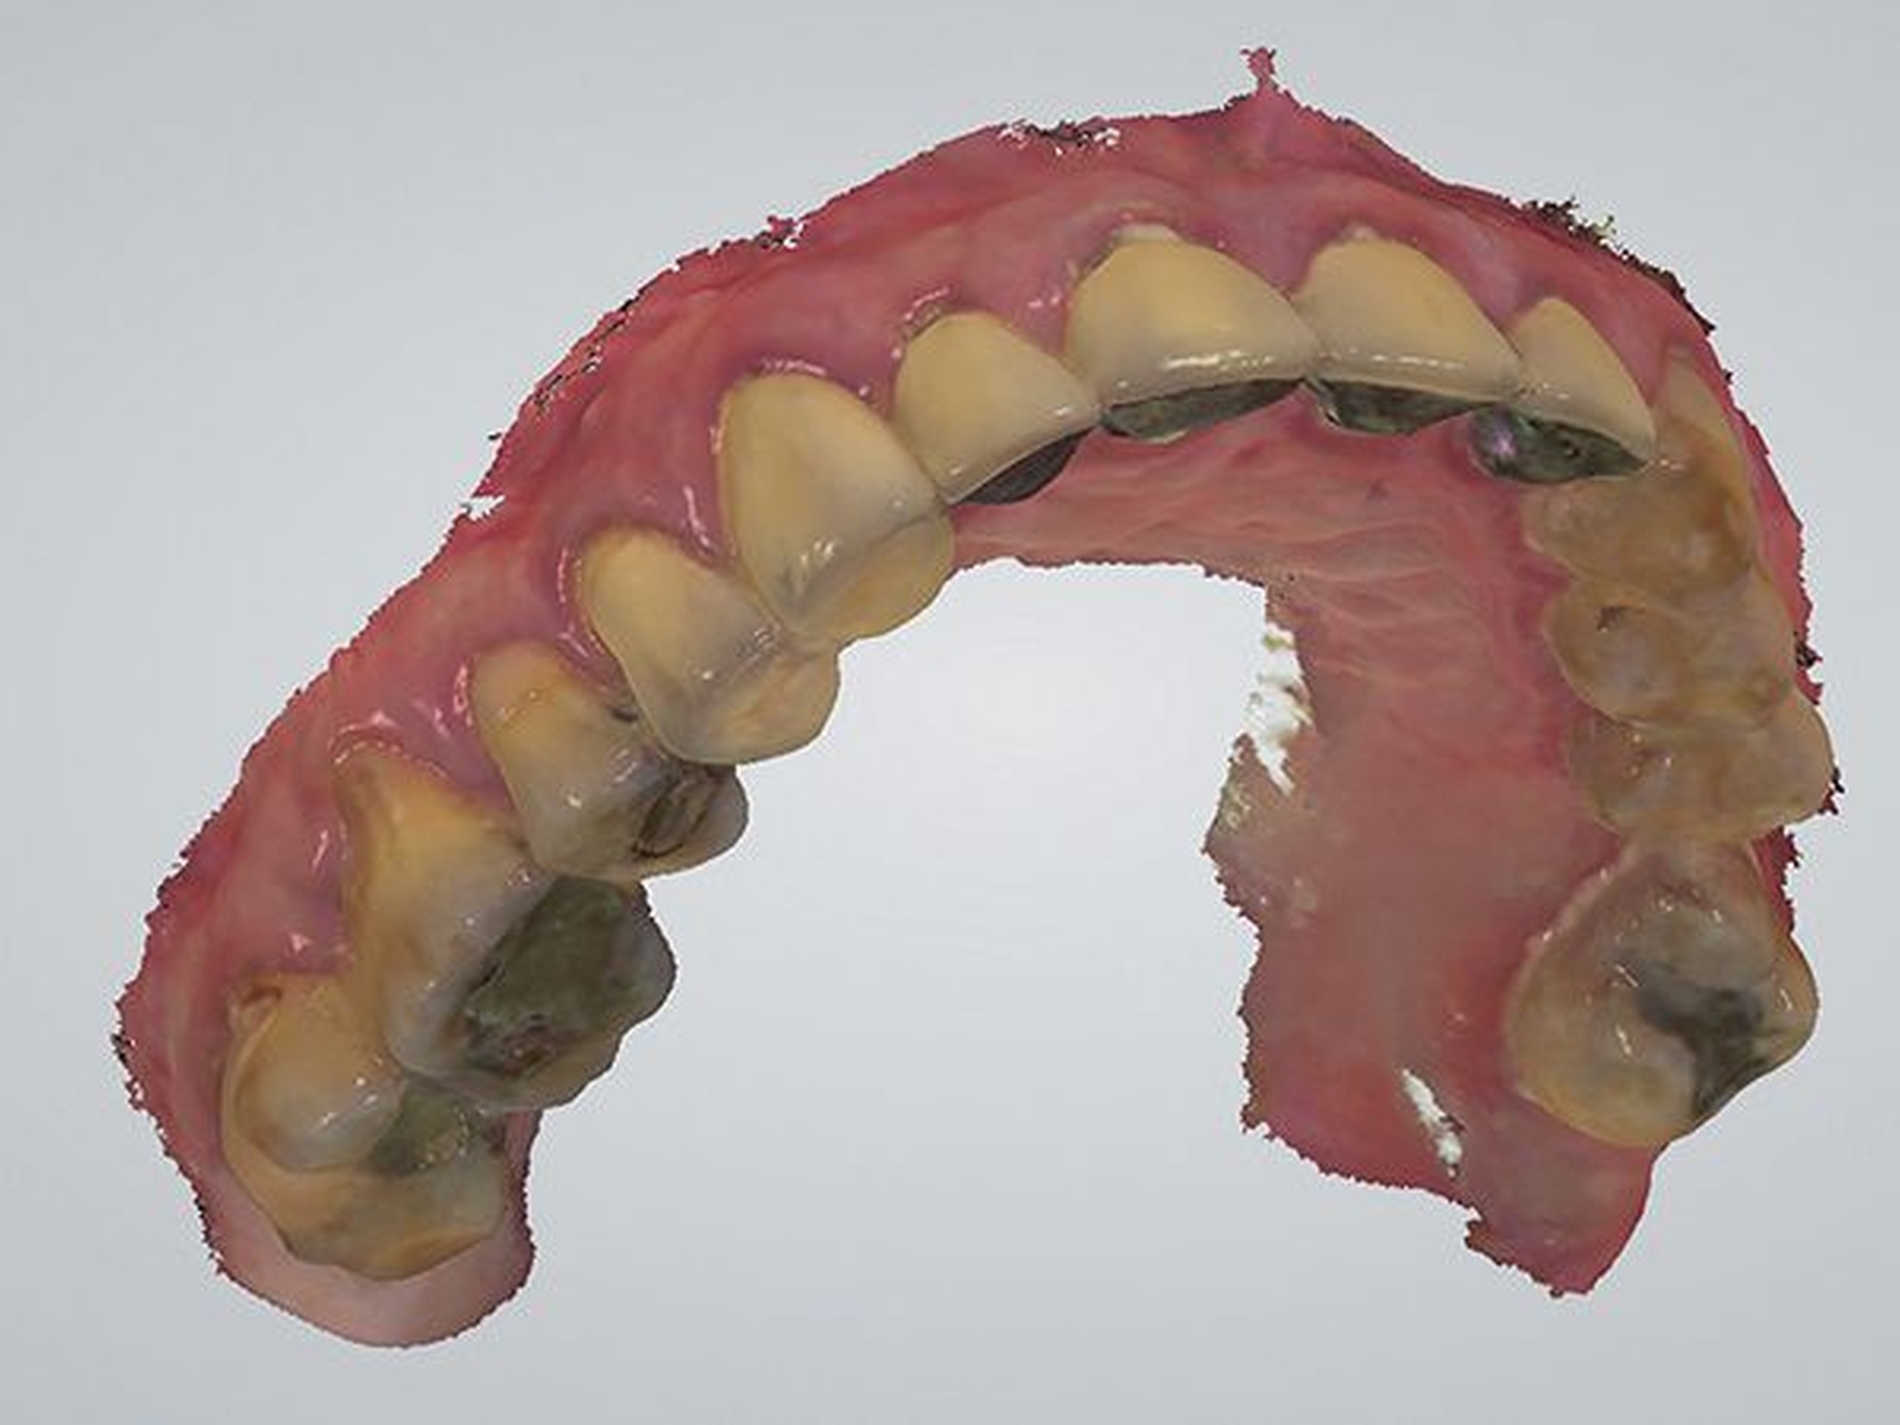

Zur weiteren Optimierung der Weichgewebe wurde die Option des Langzeitprovisoriums gewählt. Da hier eine hohe Qualität erforderlich ist, wurde die Herstellung über CAD/CAM-Technologie im zahntechnischen Labor durchgeführt. Ausgangsdatensatz war ein Scan vom Ober- und Unterkiefer. Mit dem Intraoralscanner TRIOS 3 (3Shape, Kopenhagen) erfolgten die entsprechenden Scans. Zur Verifikation der Implantatposition finden Scankörper Anwendung (Abbildungen 15, 16 und 17).

Der vom Scanner generierte Datensatz wurde vom ZTM S. Schuldes, M.Sc. in der Software DentalDesigner (3Shape, Kopenhagen) aufgearbeitet und die virtuelle Rekonstruktion der vollanatomischen Brückenversorgung begann. Die Okklusion kann dabei in Bezug zum Gegenkiefer durch multiple Ansichten optimal gestaltet werden (Abbildung 18).

Durch die Limitierung der verfügbaren Rohlingfarben wurde diese in Bezug auf den Gegenkiefer in A3 gewählt. Im CAD/CAM Verfahren wurde die Planung als verschraubte Brücke in einer CNC-Fräsmaschine mit entsprechenden Parametern für Drehzahl, Zustellung und Vorschub aus dem PMMA subtraktiv herausgearbeitet. Nach dem Fräsvorgang muss die Brücke manuell aus dem Rohling herausgetrennt und konditioniert werden.

Im nächsten Arbeitsschritt wurde die Brücke intraoral mit korrespondierenden Abutments der jeweiligen Implantate verbunden. Den Abschluss bildete die zahntechnische optische Optimierung (Abbildung 19).

Diese gesamte Konstruktion konnte dem Patienten mit einer hohen Passgenauigkeit eingegliedert werden. Die Abbildung 20 zeigt die annehmbare Farbwahl für ein Langzeitprovisorium in Bezug zur Bezahnung im Oberkiefer.

Abbildungen 20 und 21 zeigen die gesamte Brückenkonstruktion in Bezug zu den Weichgeweben. Der Patient ist mit komplett aufgebauten Stützzonen und einer vollständigen zirkulären Zahnreihe rehabilitiert.